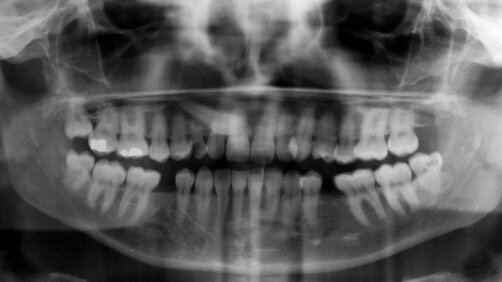

Figs. 1 & 2: Initial situation: caries destruction of upper milk canine and included canine underneath.

The radiographic examination revealed an included final canine (tooth 13) and a minimum root support of the milk canine but no presence of periapical defects (Fig. 2). The patient desired a fast and aesthetic restoration of the affected tooth.